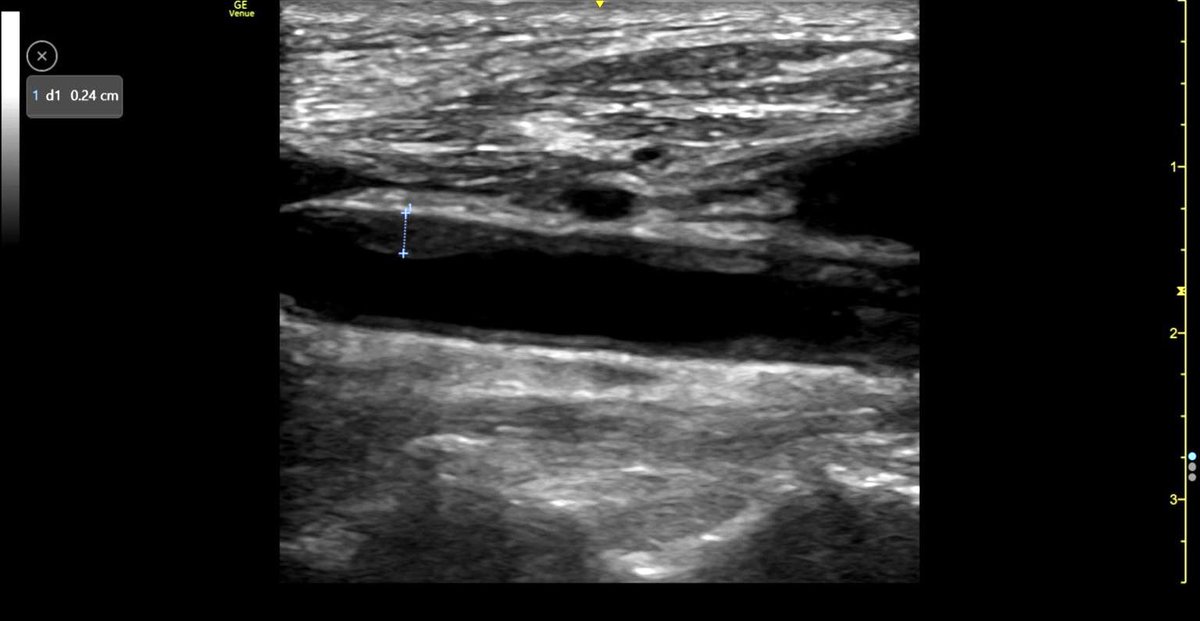

Thank you to everyone who attended, supported, and taught on our Wessex FAMUS-Lung Supervised Scanning Day. We really appreciate all your help!